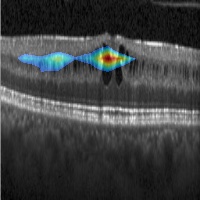

Figure 2: DME detection. Sample ROI outputs for training with different ratios of labeled images and local annotation for DME (rows 1,2) and normal (row 3) cases.

The ROIs derived with models trained using different ratios (1:R) of images with labels and with labels + localisation annotation are shown for 3 sample test images in Fig.2. The results for Mbsubscript𝑀𝑏M_{b} (last column) are diffuse ROI covering almost the entire image. With the addition of more and more images with localisation information during the training phase, the ROIs improve progressively and we get the best overlap with the FFRs when R reaches 1. The intersection over union (IOU) metric was used to help quantitatively assess the derived ROIs against the ground truth for FFR. An IOU threshold of 0.3 is taken to declare correct detection of ROI. Table 2 lists the number of correctly detected ROIs and the accuracy of detection(Correct ROIs/Total Images). These results are consistent with the qualitative results showing an increasing trend in accuracy of detection as R value approaches 1. Lowest ROI detection accuracy is obtained by Mbsubscript𝑀𝑏M_{b} due to lack of information about suspect regions during training.